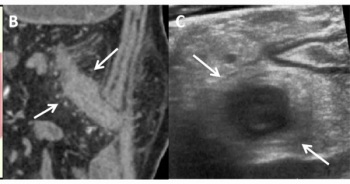

Intestinal ultrasound demonstrated an 88.2 percent agreement with computed tomography enterography in characterizing creeping fat in patients with Crohn’s disease, according to new research.